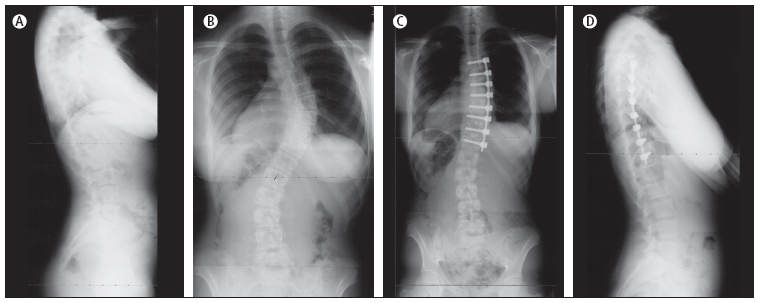

Figura

7. Radiografia di un bambino di10 anni, scheletricamente

immaturo, la cui curva toracica è progredita da 35° a 42°

nonostante il busto.

A.

Radiografia posteriore-anteriore dopo aver posto il busto; B.

Radiografia postero-anteriore, tre anni dopo l'intervento, con un

angolo di Cobb di 28°. Radiografia laterale postoperatoria; C.

Radiografia laterale, tre anni dopo l'intervento.